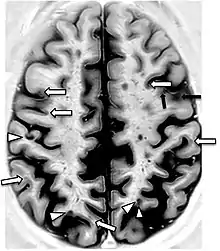

A 2019 literature review identified hypertension and history of pre-eclampsia as significant risk factors for the accelerated decline of cognitive function in women during midlife. Although the mechanism remains unclear, neuroimaging studies included in the review found that those with hypertension have evident structural changes in their brains; specifically, gray matter brain volume decreased and white matter hyperintensity volume increased.[18]